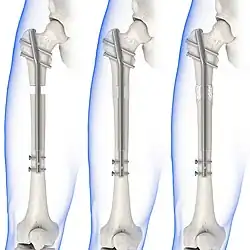

Treatment can be achieved by either non-operative (or conservative) or operative means. The main operative treatments for a Maisonneuve fracture are open-reduction surgery and closed-reduction surgery, both of which usually preceding internal fixation of the injury. These procedures are known as Open Reduction Internal Fixation (ORIF) and Closed Reduction Internal Fixation (CRIF).[6][13]

Internal fixators

Syndesmotic screws are the main, internal fixators used in surgeries for a Maisonneuve fracture. Two main types of syndesmotic screws are used: trans-syndesmotic screws (positioned at the level of the syndesmosis) and supra-syndesmotic screws (positioned above the syndesmosis).[14]

Based on several clinical results, syndesmotic screws are recommended to be fixed at least 1 centimetre proximal to the tibiofibular syndesmosis or 4 to 6 centimetres proximal to the tibiotalar joint line.[4][15] Cadaveric analyses, from a comparative study published in Foot & Ankle International in 1997, suggest that screw fixation at 2 centimetres proximal to the tibiotalar joint line is also adequate.[16] Biodegradable implants such as bioabsorbable screws, which do not require postoperative removal, may be used as an alternative to metallic hardware. However, biodegradable implants still limit rotation of the ankle and dorsiflexion of the foot.[4][6][13]

Open-reduction surgery is typically not performed at the level of the proximal fibula, as dissection near the proximal end may risk severing the common peroneal nerve. Instead, reducing the proximal fibula at the level of the distal tibiofibular syndesmosis is recommended.[6][12] A hook test is performed, using a curved hook, to assess the stability of the fibula. If instability is detected, further distraction of the fibula can be done to repair the full bone. The fibula can then be guided into the fibular notch located on the tibia, effectively restoring its length. Internal rotation of the foot may then be used to correct anatomical alignment.[12][13]

Following open-reduction, internal fixation is usually performed to stabilise the ankle mortise. To account for the distal fibula being slightly posterior to the distal tibia, drill holes are angled at 30° from the anteromedial aspect of the tibia to the posterolateral aspect of the fibula.[4][12][15] Trans-syndesmotic screws can be inserted in this way to ensure tibia fixation. Additional supra-syndesmotic screws may be temporarily inserted, for approximately 3 to 6 months, if instability is still present after fibular reduction. To reduce the fibula and restore the ankle mortise to its proper anatomical configuration, partial dorsiflexion of the foot is maintained prior to intraoperative screw fixation. This is because, in a neutral or maximally dorsiflexed position of the foot, the trochlear surface of the talus may reduce maximal postoperative dorsiflexion due to rigidity after screw fixation.[9][12]